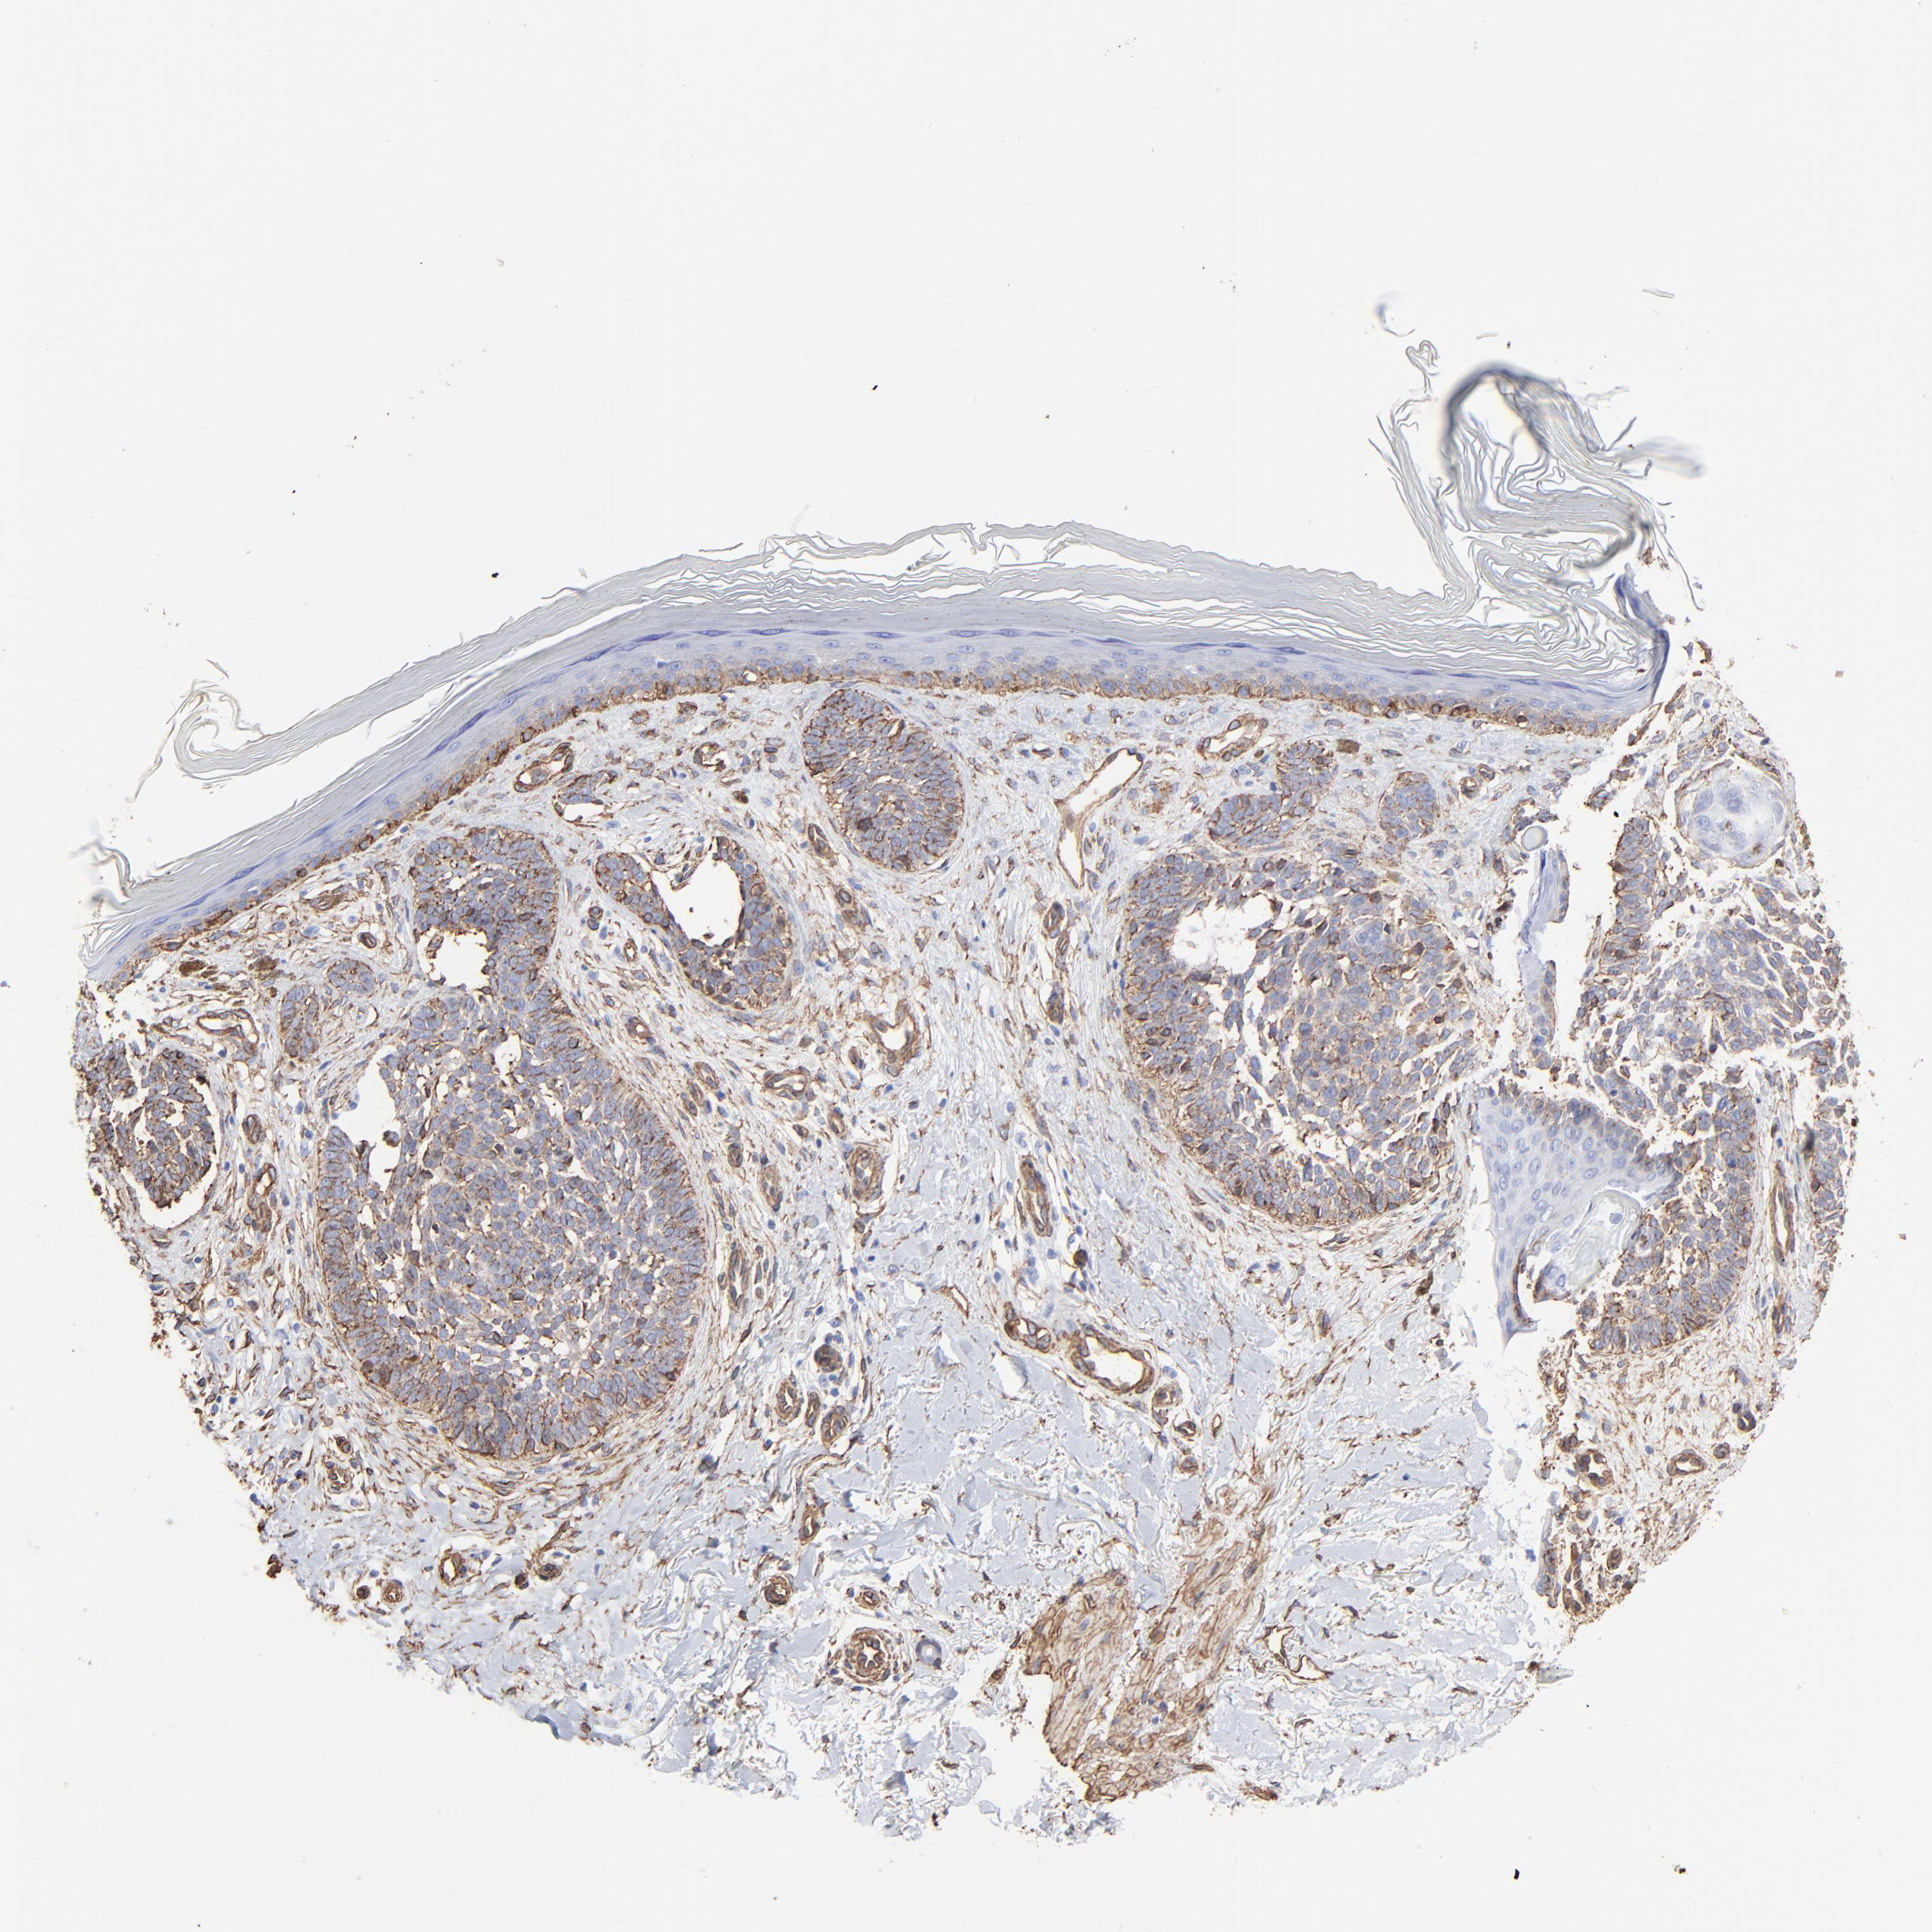

SKIN CANCER - Protein expressioni

A mouse-over function shows sample information and annotation data. Click on an image to view it in a full screen mode. Samples can be filtered based on level of antibody staining by selecting one or several of the following categories: high, medium, low and not detected. The assay and annotation is described here.

Antibody stainingi

Antibody staining in the annotated cell types in the current human tissue is reported as not detected, low, medium, or high, based on conventional immunohistochemistry profiling in selected tissues. This score is based on the combination of the staining intensity and fraction of stained cells.

Each image is clickable and will lead to virtual microscopy that enables deeper exploration of all samples and also displays staining intensity scores, fraction scores and subcellular localization as well as patient and tissue information for each sample.

Antibody HPA049326

Antibody CAB003791

Basal cell carcinoma

Squamous cell carcinoma, NOS